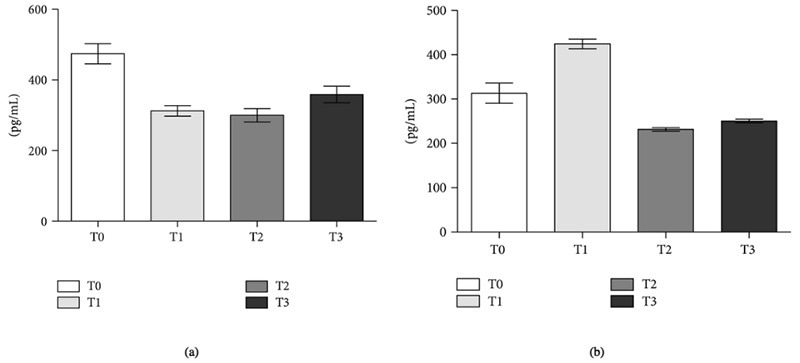

Egidi et al. measured KLKs (hK11 and hK13) in preoperative and postoperative serum samples from patients with prostate cancer using human KLK11 and KLK13 ELISA kits (Sino Biological). They discovered a significant decrease in KLK in the postoperative serum. In a different investigation, Hashemipour et al. found that lysate from 293T cells transfected with KLK10 and KLK11 (Sino Biological) were used as controls to determine the high expression of human tissue kallikreins in pleomorphic adenomas and mucoepidermoid carcinomas.

Human KLK11 and KLK13 ELISA antibody pair sets (Sino Biological) were used to measure hK11 (Panel a) and hK13 (Panel b) levels (pg/mL ± SE) in sera from patients with localized prostate cancer. T0: preoperative time; T1: 1st postoperative day; T2: 5th postoperative day; T3: 30th postoperative day. Image Credit: doi.org/10.1155/2013/241780